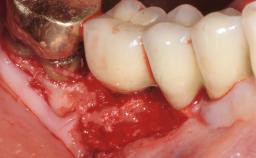

In this case, Myroslav Solonko, Ignacio Sanz Sánchez and Mariano Sanz present a treatment that aims to eliminate exposed implant threads by modifying the implant surface, converting a moderately-rough surface into a smooth surface.

A 63-year-old male patient was referred to the post-graduate periodontal clinic of the Complutense University of Madrid for the treatment of peri-implantitis. According to the patient’s record, all his maxillary teeth had been extracted ten years previously due to severe periodontitis, and a full-mouth implant-supported restoration on eight implants was placed. No supportive periodontal therapy was provided apart from occasional check-ups by the restorative dentist.